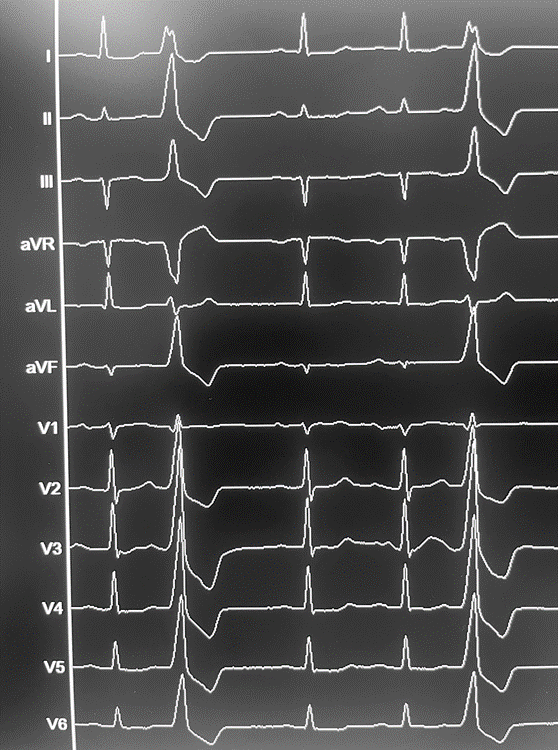

Abbildung 1: Monomorphe VES: Inferiore Achse, positive Konkordanz

Im 12-Kanal EKG zeigt sich die folgende Morphologie: Inferiore Achse (II, III, aVF: positiv), positive Konkordanz (V1-V6: positiv). Das EKG weißt auf einen Ursprung im Ausflusstrakt des Herzens (Inferiore Achse) und damit auf eine idiopathische Genese hin. Der Focus ist bei einer positiven Konkordanz der Brustwandableitungen am ehesten im linksventrikulären Ausflusstrakt (LVOT) lokalisiert. Gemeinsam mit der Patientin wurde ein invasives Vorgehen mittels Katheterablation vereinbart. In der Prozedur wurde mittels hochauflösendem 3D-Mapping (Carto 3, Biosense Webster) zunächst der LVOT im Bereich unterhalb der Aortenklappe über einen transseptalen Zugangsweg untersucht. Hier war keine gute Vorzeitigkeit der Erregung nachweisbar (max. 15ms). Daher erfolgte ein hochauflösendes 3D-Mapping der Aortenwurzel per transaortalem retrogradem Zugang via Art. femoralis. Innerhalb der rechts coronaren Aortentaschenklappe (RCC) war eine Vorzeitigkeit von 35ms messbar.